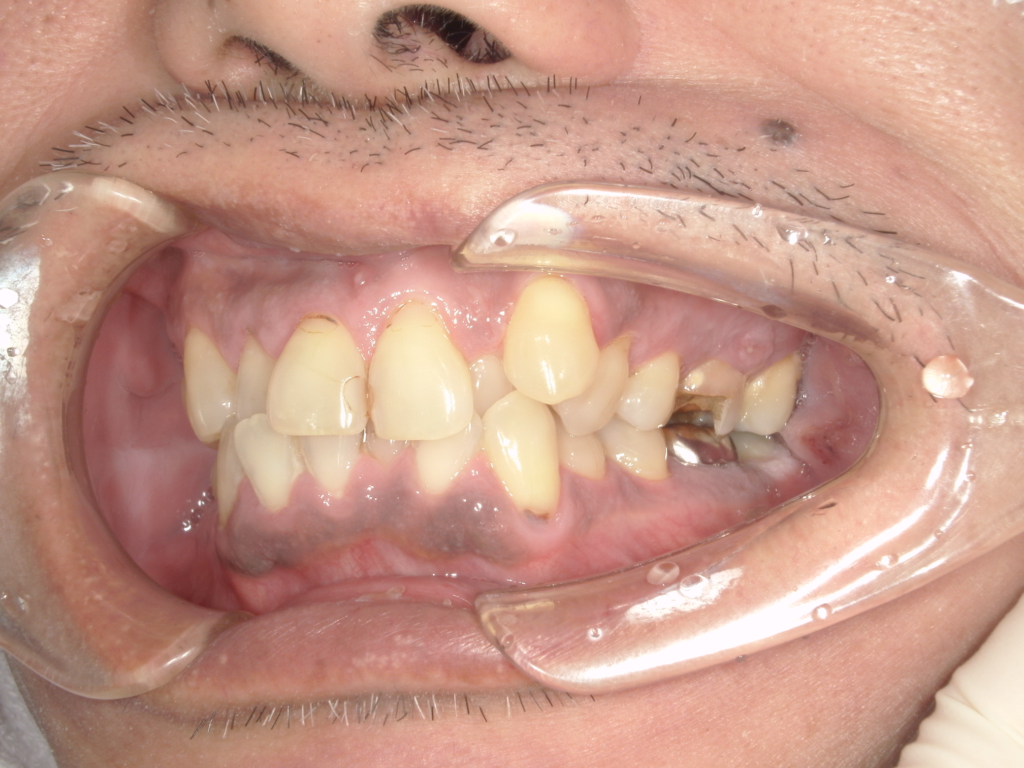

Y様インプラント実例 #44

左の上下の奥歯をインプラントで治療しています。

左下の奥歯は歯を抜くのと同時にインプラントの埋め込みを行っています。

被せものは上下、セラミックスで作っています。

治療前

治療後